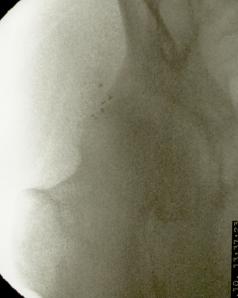

La artroplastia total de cadera para los casos de coxartrosis severa es el tratamiento de elección de la gran mayoría de cirujanos ortopédicos. Sin embargo cuando el paciente es menor de 50 años suele diferirse la intervención debido al tiempo de sobrevida del material protésico. También lo es en pacientes con deterioro del estado general debido a la avanzada edad o a enfermedades concomitantes (cardiópatas, por ej.) En estos casos la colocación de microimplantes de oro periarticulares alrededor del cuadrante súpero externo de la articulación es, habida cuenta del resultado sintomático y funcional, el tratamiento más indicado. La fácil colocación mediante control radioscópico y la rapidez de la recuperación (inmediata) hacen que este procedimiento sea seguro y muy útil para la remisión del dolor y la rigidez. No necesita ingreso ya que es una cirugía ambulatoria, se efectúa con anestesia local, y el paciente sólo requiere reposo relativo en el día de la intervención. Los resultados mediatos son excelentes. La mejoría clínica aumenta con los meses debido a la difusión de las nanopartículas de oro, por lo que contrariamente a los tratamientos convencionales que disminuyen su efecto con el tiempo, los microimplantes de oro lo mejoran. En cuanto esta técnica se popularice se reducirá significativamente el número de artroplastias.

Más abajo se observarán unas imágenes de casos de implantes de oro en cadera